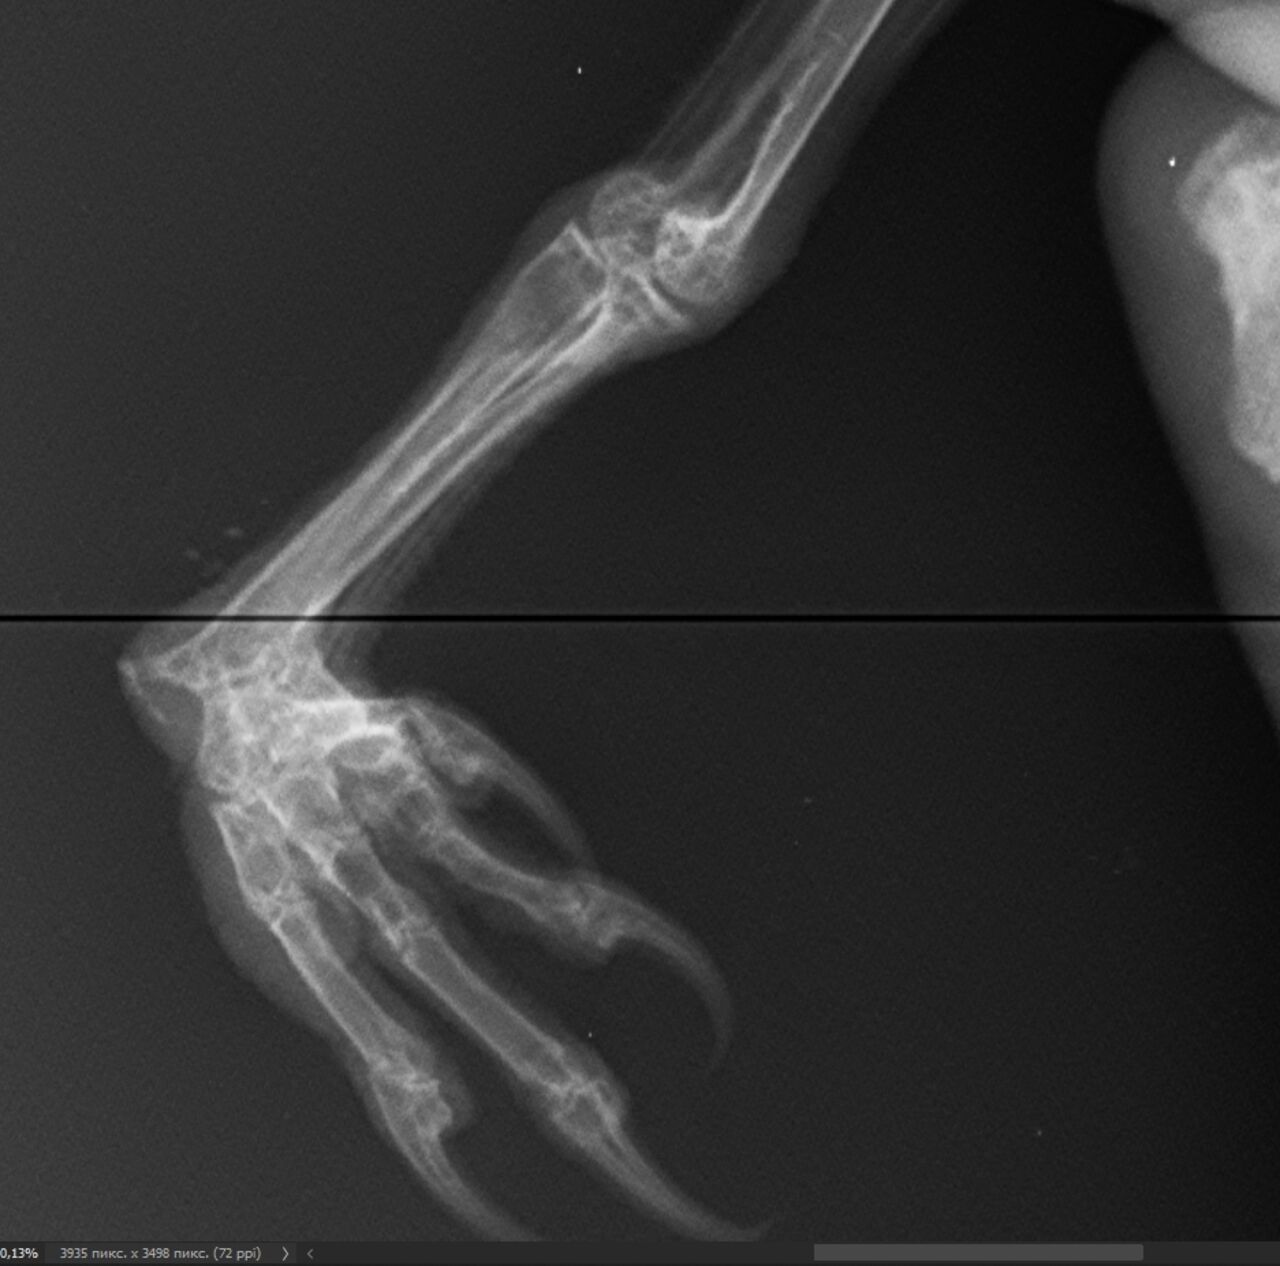

Обследование показало, что сова ушиблась вся целиком, а еще у нее перекошенная лапа – вероятно, сломалась и неправильно срослась еще в гнезде. Для спасения животного пришлось покупать нечто неожиданное – аппарат для маникюра и педикюра.

– Купили микромотор, но не для совиного маникюра, хотя хотелось бы, а чтобы выполнять некоторые хирургические манипуляции с костями, – пояснили в центре.